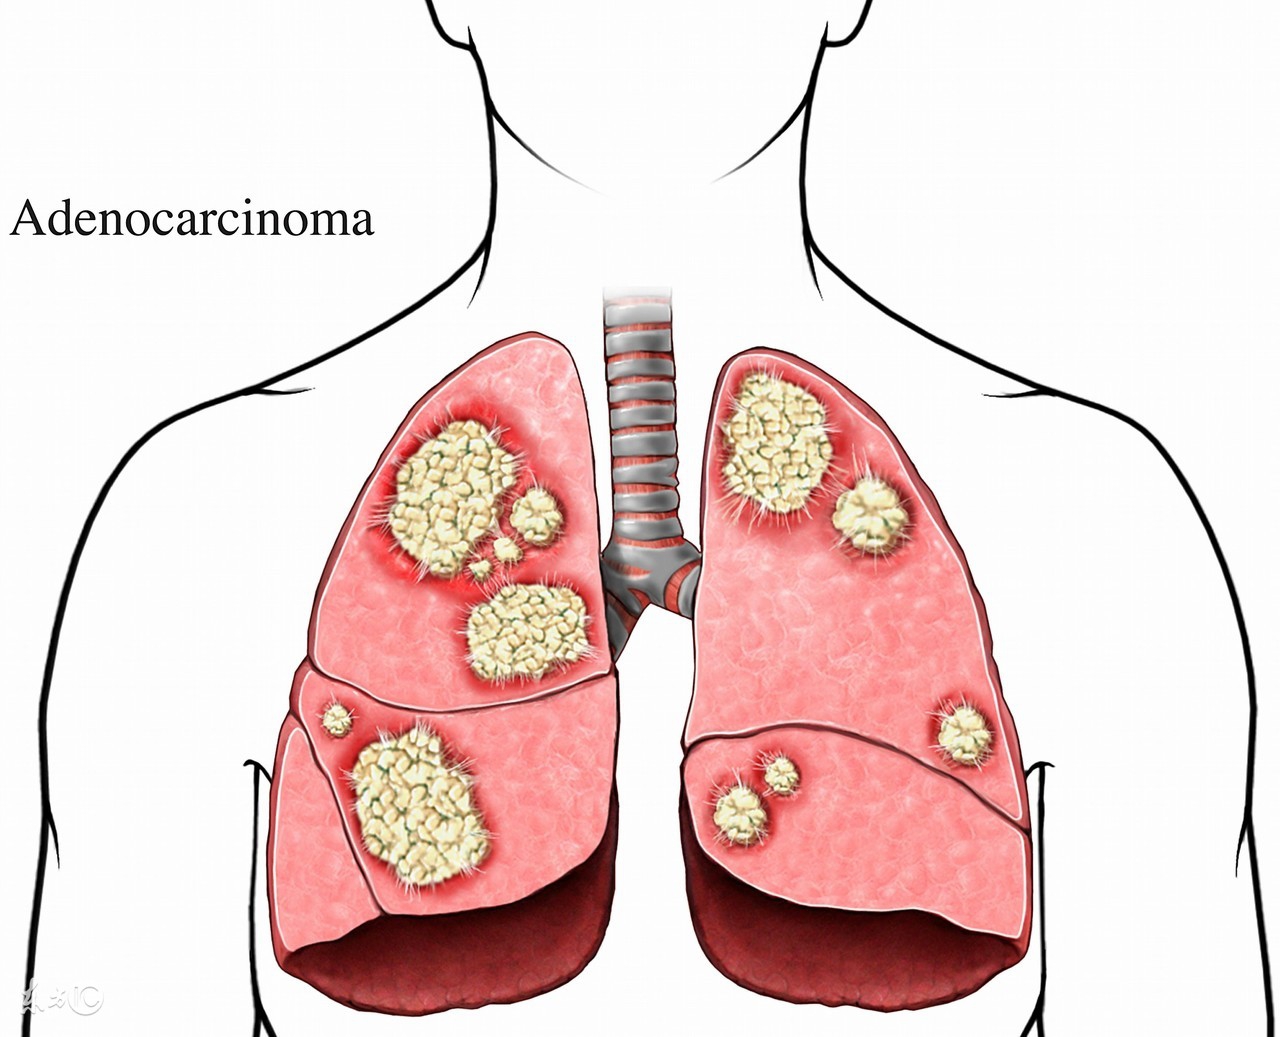

肺假性肿瘤不是肺癌,它只是一种良性肿瘤。肺假性肿瘤也叫作肺炎性假瘤,主要是因为肺部炎性物质导致的肉芽肿、机化、纤维结缔组织增生,和其肺部疾病导致肺部肿块。

很多来呼吸科就诊的患者中,很多人都存在肺假性肿瘤这一疾病,大都惊慌,担心癌变,一直询问医生是不是肺癌。其实肺假性肿瘤不是肺癌,只是一种常见的肺部良性肿瘤而已,不必过于担心。

肺假性肿瘤不是肺癌,被检测出肺假性肿瘤的患者不用过于焦虑担忧,积极的配合医生治疗即可。